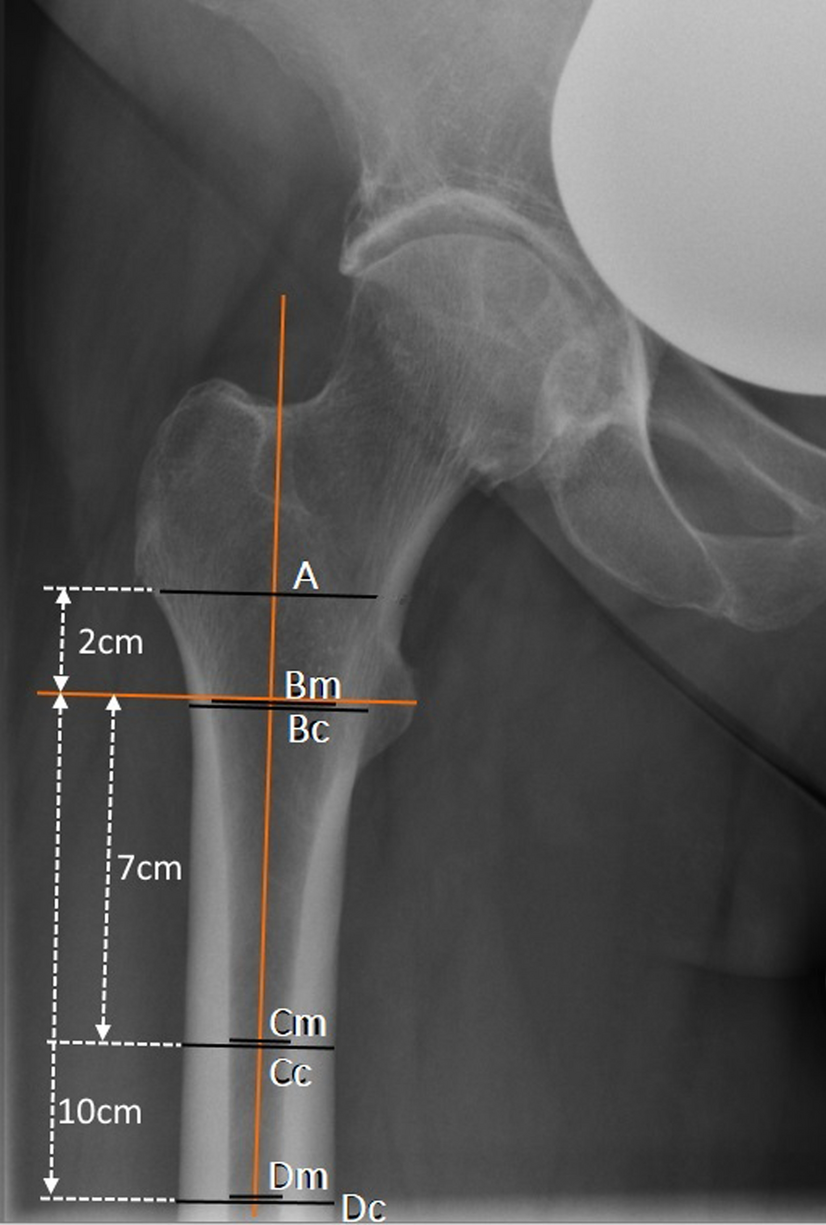

Measurement of the indices on plain ap radiographs: canal-bone-ratio CBR-7 cm (= Cm/Cc) and CBR-10 cm (= Dm/Dc), canal-calcar ratio CCR (= Dm/Bm); canal flare index CFI (= A/Dm).